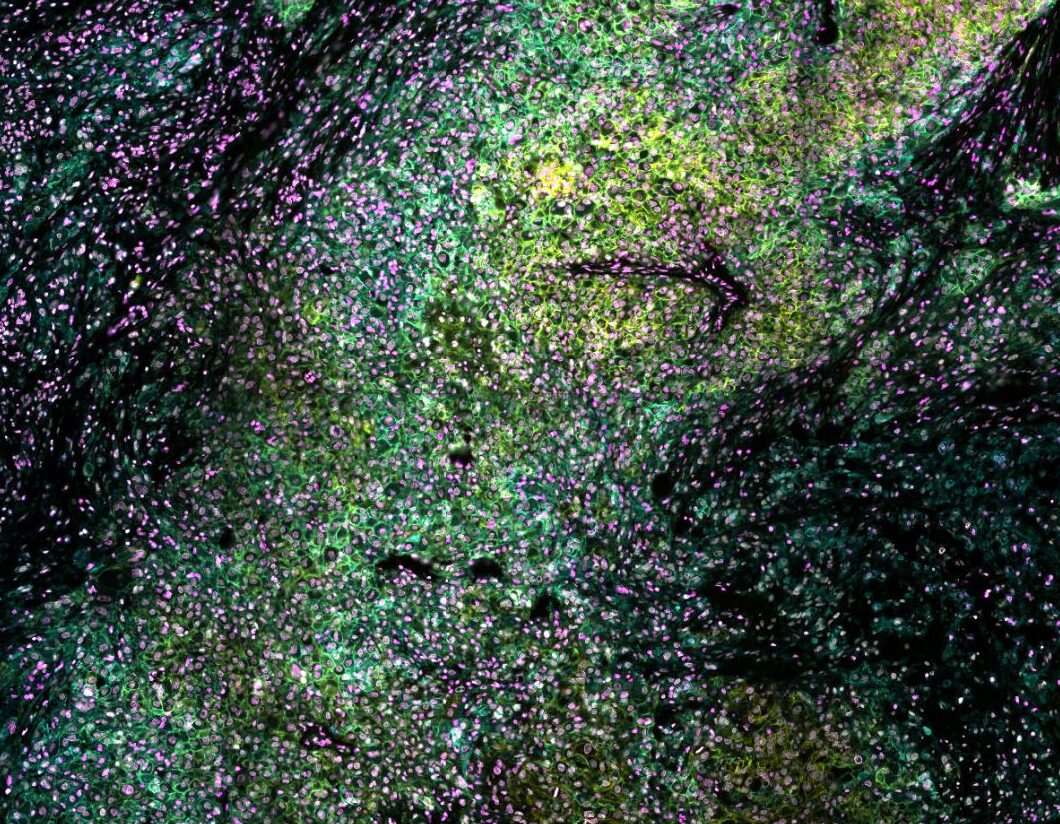

The CellScape Data Explorer gives you an interactive, in-browser view of real high-plex spatial proteomics datasets generated with VistaPlex™ Assay Kits and the simple, straightforward CellScape platform workflow. Each dataset showcases the CellScape platform’s ability to capture broad tissue architecture and unparalleled cellular detail within the same field of view, letting you zoom seamlessly from large-scale structure to single-cell features while maintaining best-in-class resolution and high dynamic range.

Across all datasets, you can toggle individual markers, survey vast or precise regions of tissue, and see real-world data from each of our VistaPlex Multiplex Assay Kits to evaluate staining specificity and marker localization. Integrated phenotype and segmentation overlays help you quickly visualize cellular organization, tissue compartments, and spatial relationships, providing a clear sense of panel performance and biological resolution without needing to download any files.